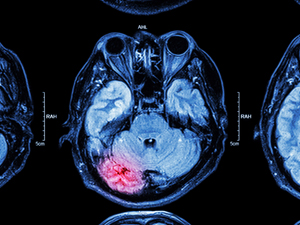

Актуальність проблеми цереброваскулярних захворювань полягає в поширеності інсультів як провідного чинника смертності та погіршення якості життя в популяції. Незалежно від етіології гострого розладу мозкового кровообігу, патогенетичною ланкою ішемічного інсульту залишається порушення прохідності мозкових судин різного калібру. Слід зазначити, що до 10% ішемічних інсультів викликає оклюзія судин у ділянці вертебро-базилярного басейну. Клінічна важливість проблеми оклюзії вертебро-базилярних судин зумовлена її кардинальністю та істотним впливом на рівень смертності та інвалідизації пацієнтів [2]. Разом з традиційною фармакотерапією сучасний підхід до лікування ішемічного інсульту полягає в проведенні інтервенційного ендоваскулярного тромболізису [3]. Спираючись на позитивні результати попереднього рандомізованого дослідження, яке продемонструвало позитивний вплив інтервенційної процедури ендоваскулярного тромболізису у пацієнтів з оклюзією судин переднього сегменту мозкового кровообігу, група дослідників з Лікарні Святого Антонія, м. Ньівегейн, Нідерланди, поставила за мету дослідити ефективність та безпеку ендоваскулярного тромболізису у пацієнтів з оклюзією великих судин вертебро-базилярного басейну [1]. Результати опубліковані в журналі «Медичний журнал Нової Англії» («New England Journal of Medicine»).

Дослідження проводили за участю 300 пацієнтів з ішемічним інсультом в вертебро-базилярному басейні. Їх було поділено на дві співставні за чисельністю групи. Пацієнти з групи фармакотерапії отримували медикаментозне лікування відповідно до актуальних узагальнених рекомендацій (146 пацієнтів); 156 пацієнтів лікувалися методами інтервенційної кардіохірургії. У якості первинної кінцевої точки дослідження визначили сприятливий функціональний результат, який оцінювали через 3 міс після лікування за шкалою Ренкіна (Rankin rate) за кількістю балів рухових порушень. Вторинною кінцевою точкою дослідження зазначили клінічну відповідь на лікування, яку оцінювали шкальним методом за бальною оцінкою тяжкості рухових та когнітивних порушень в першу добу після початку лікування. Клінічні ознаки неврологічного дефіциту порівнювали з площею патоморфологічних змін шляхом виконання нейровізуалізуючого дослідження. Безпеку інтервенційного ендоваскулярного тромболізису оцінювали за частотою внутрішньомозкових кровотеч, які виявляли шляхом нейровізуалізації через 3 дні після початку лікування або за умови настання смерті через 3 міс, за шкалою оцінювання кровотеч Ґейдельберга. Аналіз отриманих результатів свідчить про наступне: